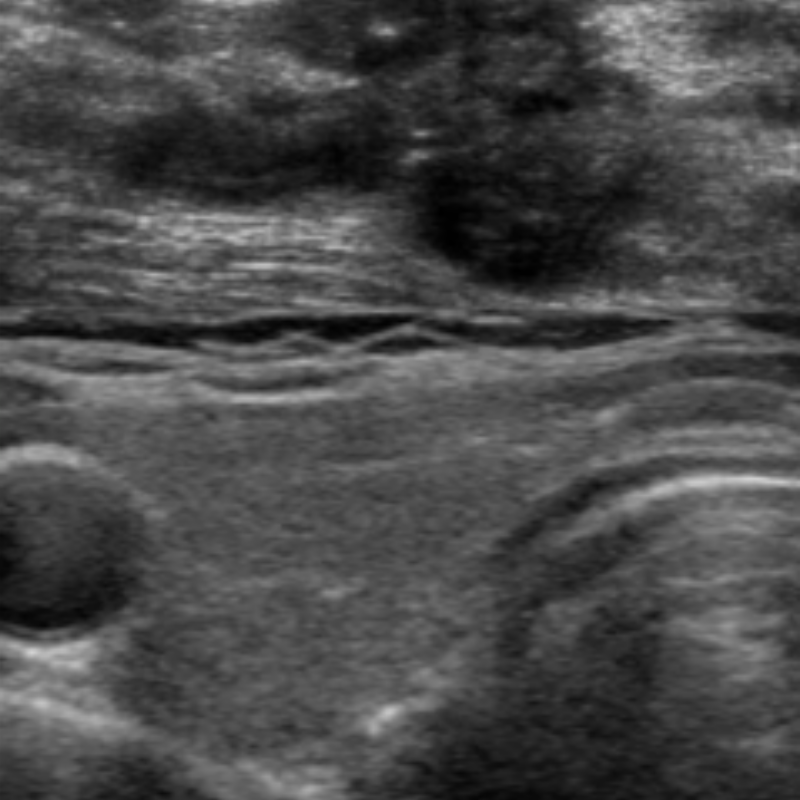

관절초음파

관절초음파는 관절 및 인대 등의 관절주변조직의 염증과

손상을 빠르고 간편하게 확인하는데 도움을 줍니다.

또한 관절을 침범하는 류마티스질환과

다른 근골격계 질환과의 감별을 용이하게 하고

초음파 유도하에 약물주입 등의 시술도 가능합니다.

01) 방사선을 사용하지 않아 인체에 해가 없다.

02) 검사를 하는 동안 실시간으로 영상을 확인 가능하다.

03) X-ray로 확인이 어려운 초기 관절염증을 진단하는데 도움된다.

04) CT나 MRI 등의 검사에 비해 쉽게 사용 가능, 비용이 저렴하다.